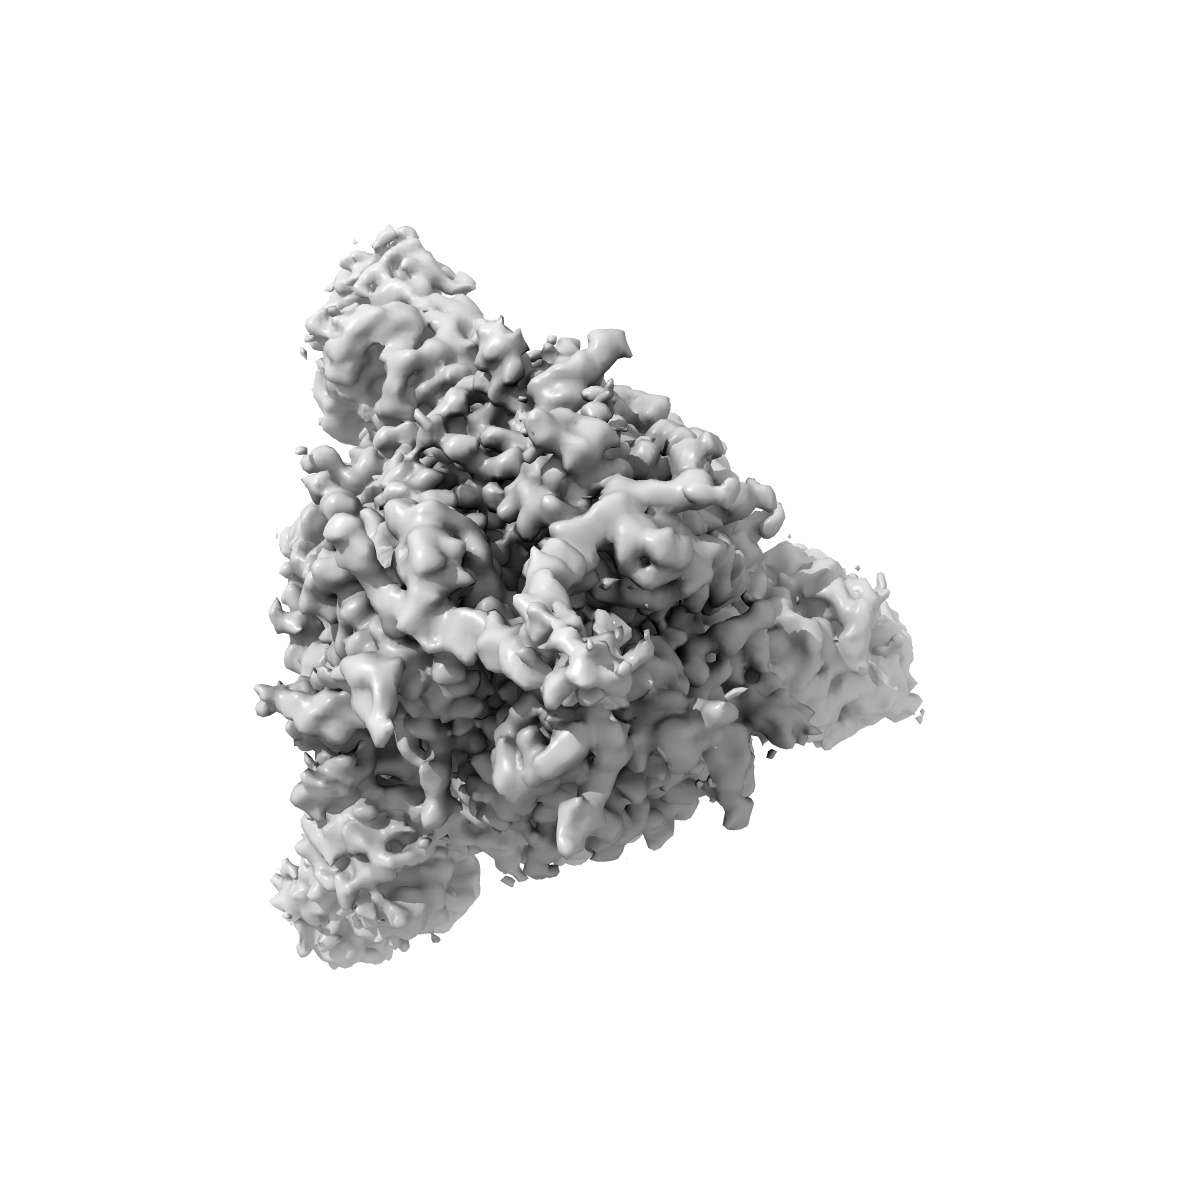

Delta (B.1.617.2) SARS-CoV-2 variant spike protein (S-GSAS-Delta) in the 3-RBD-down conformation; Subclassification D8 state

Single-particle3.57 Å

Sample: Delta (B.1.617.2) SARS-CoV-2 variant spike protein (S-GSAS-Delta) in the 3-RBD-down conformation; Subclassification D8 state

Structural diversity of the SARS-CoV-2 Omicron spike.

(2022) Mol Cell , 82 , 2050 - 2068.e6